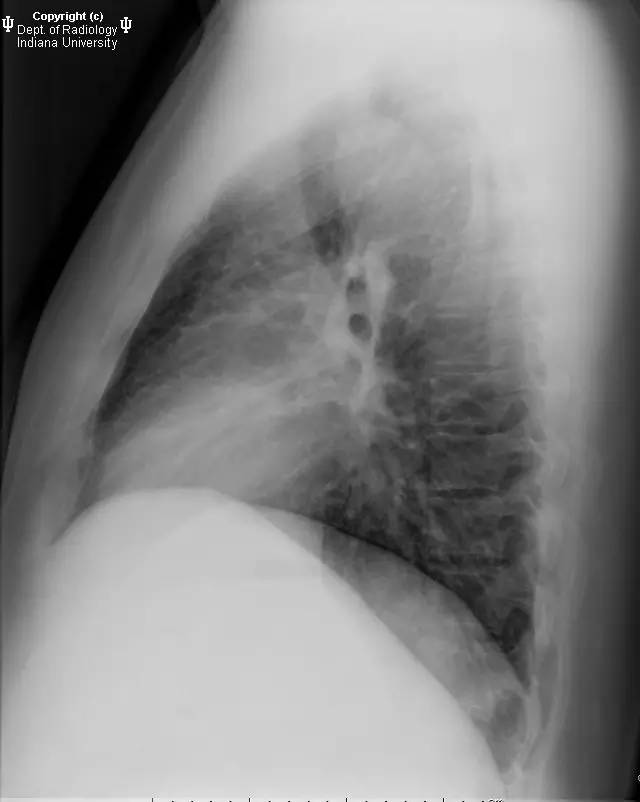

【影像学表现】胸部平片示右位主动脉弓,肺动脉突出,双肺清晰。CT示右位主动脉弓,并右位降主动脉,迷走左锁骨下动脉起自后方,从食管后走形形成血管环。迷走左锁骨下动脉与憩室相关(Kommerell)。食管因左锁骨下动脉及憩室而向前移位。

【诊断】右位主动脉弓并血管环形成、迷走左锁骨下动脉并Kommerell憩室

Right-sided aorticarch, with vascular ring and aberrant left subclavian with Kommerell\’sdiverticulum